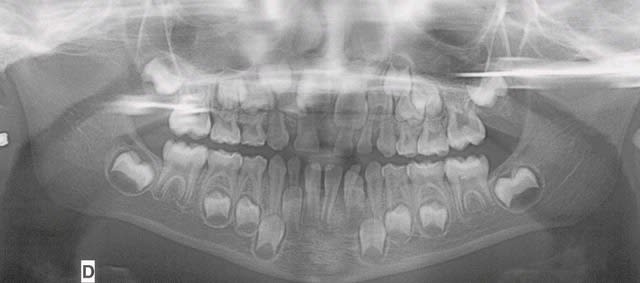

Pano2001 fote46 - Eugenol

Pano2007 pmbvzt - Eugenol